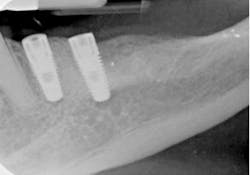

Fig. 17ConclusionBy incorporating the Tack & Wave technique into their clinical protocol, dentists can realize a convenient and effective way to remove excess cement from restoration margins and interproximal areas when placing all-ceramic veneer restorations. New resin cement systems now available make it easy to set resin in a “semi-gel” state, so clinicians can initially place veneers without them drifting and subsequently quickly and easily peel away the excess cement in more time-efficient and less technique-sensitive manner (See Figs. 18-23).

Fig. 18

Fig. 19

Fig. 20

Fig. 21

Fig. 22

Fig. 23Author bioDavid S. Hornbrook, DDS, FAACD, a gifted clinician and product researcher turned mentor, guides meeting participants to the realization that they, too, possess the ability to practice esthetic dentistry at the very highest level. He is one of dentistry’s most famous faces and one of the pioneers of live-patient, hands-on clinical education, as the founder and past director of Pac-live and the Hornbrook Group. He has been a guest faculty member of the postgraduate programs in cosmetic dentistry at Baylor, Tufts, SUNY at Buffalo, UMKC, and the UCLA Center of Cosmetic Dentistry. Dr. Hornbrook lectures internationally on all facets of esthetic and restorative dentistry and has published articles in all of the leading dental journals. A prolific researcher and materials enthusiast, he consults with numerous manufacturers on product development and refinement. Dr. Hornbrook’s warm and engaging style earns him the highest possible marks from participants and meeting sponsors.